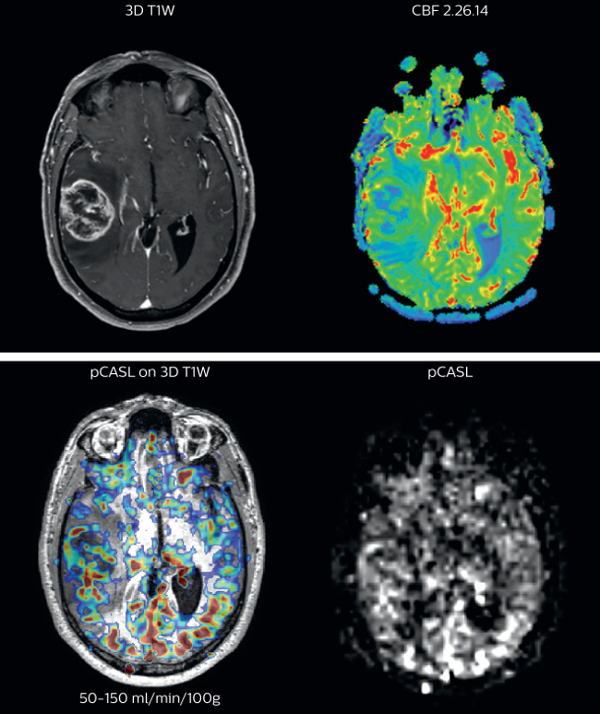

Brain perfusion imaging is typically performed using a contrast agent. However, pCASL allows visualization of brain perfusion and physiology without contrast agent injection. This fast sequence can be an alternative for perfusion imaging in patients who are contraindicated for use of gadolinium based contrast agents. “We have compared pCASL to T2*-weighted perfusion imaging with contrast agent in patientswith brain tumors”, says Dr. Nickerson. “In the cases included in our study, pCASL was at least as representative as perfusion with contrast agent. It’s a pretty big improvement if we’re avoiding giving gadolinium and we’re getting a quite equivalent dataset, that’s a pretty big improvement.”

The pCASL method is now broadly used at UVM. “It’s a short sequence, and is ideal for use in patients where motion is a concern. pCASL is currently included in all our MRI exams for patients with a known tumor, either initial or post-operative and all follow-ups. Additionally, it can also be used when we examine for stroke. And of course, pCASL is an alternative allowing perfusion imaging in patients with compromised renal systems, for whom contrast agent is contraindicated.” “Furthermore, we image a fair number of pediatric tumors here and the repeatability of pCASL is a great benefit when scanning pediatric patients with brain tumors. If the patient moves during the acquisition of a DSC perfusion scan, we missed our shot. However, if a patient moves during pCASL, we can simply repeat the scan because there’s no contrast injection involved,” says Dr. Nickerson Richard Watts, PhD, brings forward another aspect. “Quantification with pCASL does not have the issue of selecting an arterial input function like with contrast-agent based scans. In the brain tumor studies that we’ve been running, we feel it’s not sufficient just to ascertain one side has got more blood flow than the other side. In the future, we want to move towards quantitative comparisons between subjects.”

The pCASL perfusion map overlaid on the 3D T1 image demonstrates a peripheral rim of elevated cerebral blood flow corresponding to the centrally necrotic glioblastoma. The pCASL-generated CBF closely approximates the rim of elevated rCBV obtained with DSC contrast-enhanced perfusion imaging. Scanned on Achieva 3.0T dStream